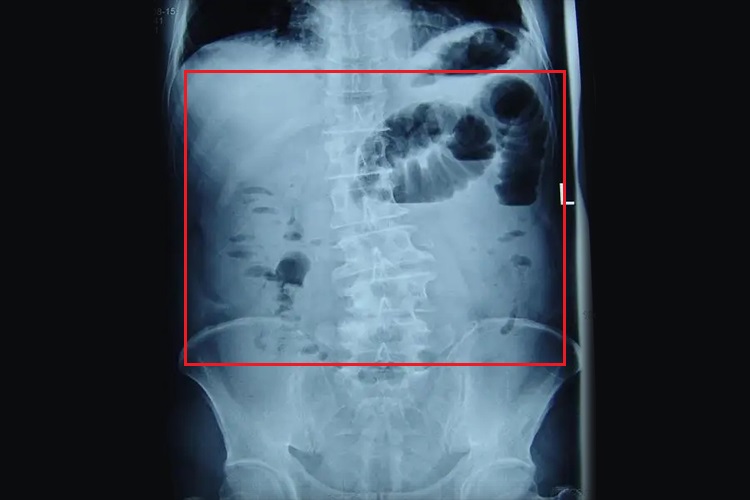

麻痹性肠梗阻仰卧位腹部平片上表现为整个胃肠道普遍性扩张,胃、小肠和结肠均见轻到中度扩大、胀气,尤以结肠胀气较明显。站立位平片上表现为在小肠和结肠内可见宽窄不等的气液平面,分布范围较广。